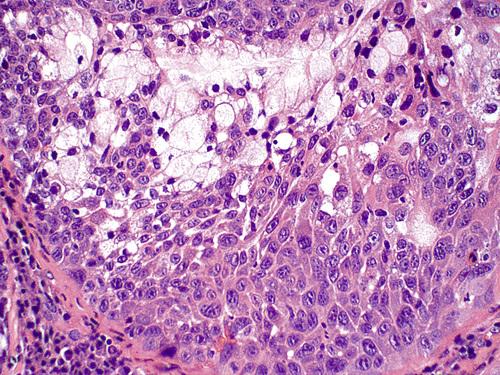

Histopathologic Features

- acinar necrosis in early lesions

- squamous metaplasia of salivary ducts

- preservation of lobular architecture

- liberation of mucin

necrotizing sialometaplasia

Necrotic mucous acini (left) and adjacent ductal squamous metaplasia (right). The overall lobular architecture of the involved glands is still preserved.

necrotizing sialometaplasia